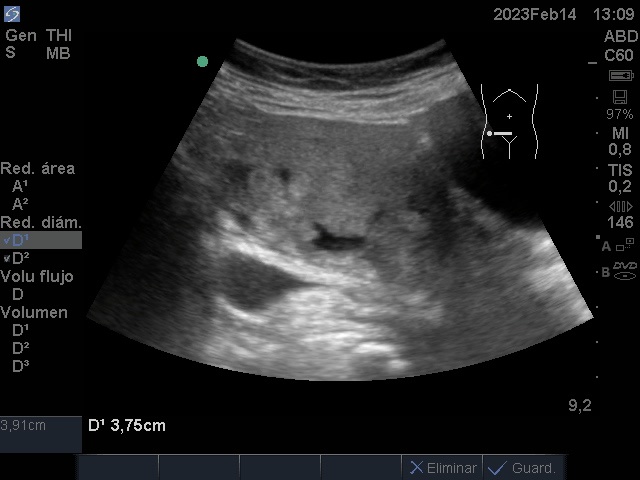

Se realiza ecografía renal y vesical en Consulta de médico de Cabecera

Hallazgos ecográficos

Útero aumentado de tamaño heterogéneo, con áreas sólido quísticas de bordes irregulares.

Ecografía transvaginal confirma útero aumentado de tamaño con paredes engrosadas, con abundante vascularizacion al aplicar dopper color. Ovario derecho: quiste anecoico de 32x26 mm.

Ovario Izquierdo: quiste de similares características 62x56 mm.